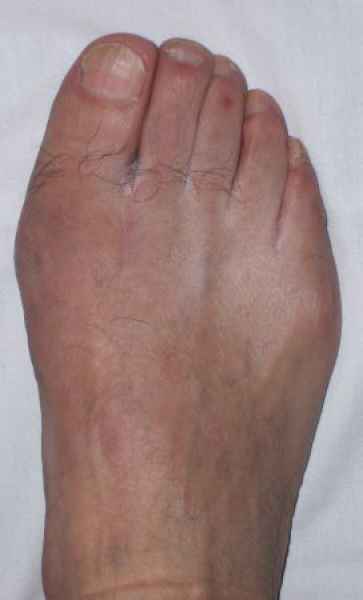

La marcha no solo es característica de la especie humana sino también de cada persona, y más aún varía según el estado de ánimo del momento. Una patología en los pies, se traduce en el rostro, en el ánimo, en el psiquismo. No sólo el dolor produce estos efectos, también un pie deformado o poco estético. En nuestra sociedad, la estética constituye un valor muy apreciado y estas alteraciones causan vergüenza fundamentalmente en las mujeres, que esconden en la playa sus pies en la arena y no pueden usar calzados elegantes.